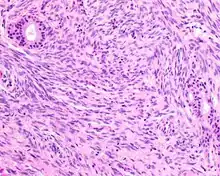

Hematoxylin and eosin stained image of a biphenotypic sinonasal sarcoma

• Infiltrative, highly cellular spindled cell neoplasm is poorly circumscribed and unencapsulated. Bone destruction or invasion is common. The cells show medium to long fascicles (nerve fibers), with a herringbone pattern. The cells are remarkably uniform with elongated nuclei. Delicate strands of intercellular collagen without ropy or dense deposition are seen. A very characteristic concurrent surface-type respiratory epithelial proliferation is found from the surface or in small cystic spaces around the cancer cells, often forming glands. The background may have a rich vascularity and usually has a small number of scattered lymphocytes. Extra growths or mitoses are rare, while necrosis, ulceration, and hemorrhage are usually absent.